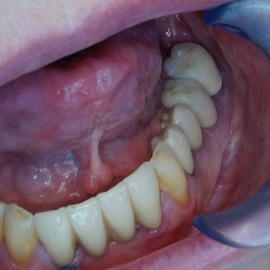

Obustronne braki skrzydłowe w żuchwie.